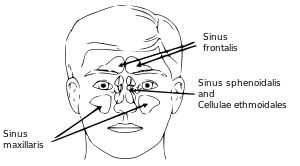

Sagittal section of nose mouth, pharynx, and larynx. Outline of bones of face, showing position of air sinuses.

Outline of bones of face, showing position of air sinuses. Paranasal sinuses